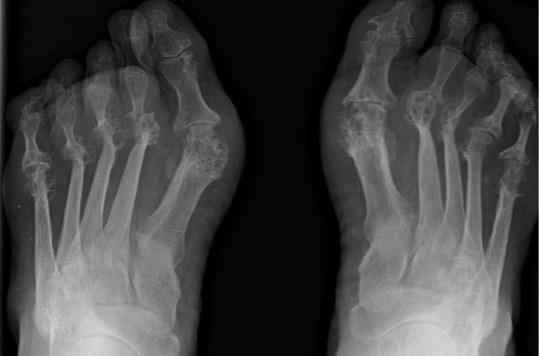

Rheumatoid arthritis

- Typically involves metatarso-phalangeal joints in a bilateral symmetrical fashion

- Early findings are soft tissue swelling, joint effusions and periarticular osteoporosis

- Progressive joint space narrowing and periarticular erosions as synovial pannus invades cartilage and bone

- Generalised osteoporosis and characteristic valgus deformities of the toes progressing to gross subluxation and dislocation in severe cases

Rheumatoid arthritis with symmetrical MTP joint loss, erosions and subluxation